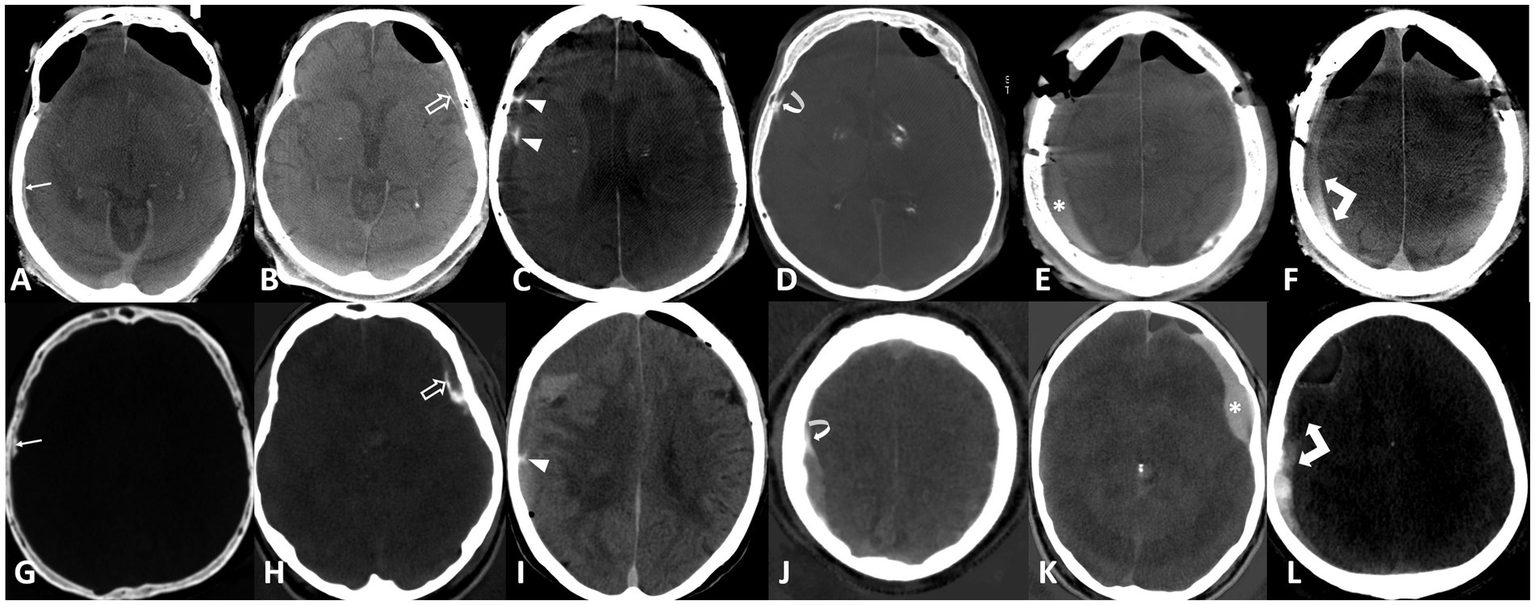

The raters evaluated the diagnostic quality of the CT images as either sufficient or insufficient, particularly due to the presence of motion artifacts. Images deemed to have sufficient quality were analyzed for the presence of hyperdensity within or around the hematoma. The raters further determined whether the hyperdensity represented hemorrhage, enhancement, or both, and rated their diagnostic confidence on a 5-point Likert scale (1 being very unsure to 5 being very sure). In cases of presumed enhancement, the raters identified all enhancing components, including the outer membrane, inner membrane, transition zone (‘spandrel sign’), septations, internal enhancement within the subdural hematoma, and fluid–fluid levels, as previously described (21). Examples of enhancement patterns are provided in Figure 2.

Figure 2

Enhancement patterns: Upper row flat-panel CT, lower row iodine maps of photon counting CT. (A,G) Outer membrane (arrows), (B,H) inner membrane (open arrows), (C,I) septations (arrowheads), (D,J) spandrel sign (curved arrows), (E,K) internal enhancement (asterisk), (F,L) fluid–fluid level (double arrows).